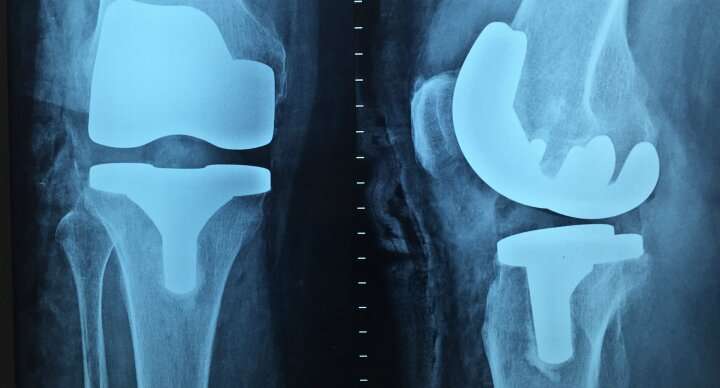

New plastic biomaterials could lead to tougher, more versatile medical implants